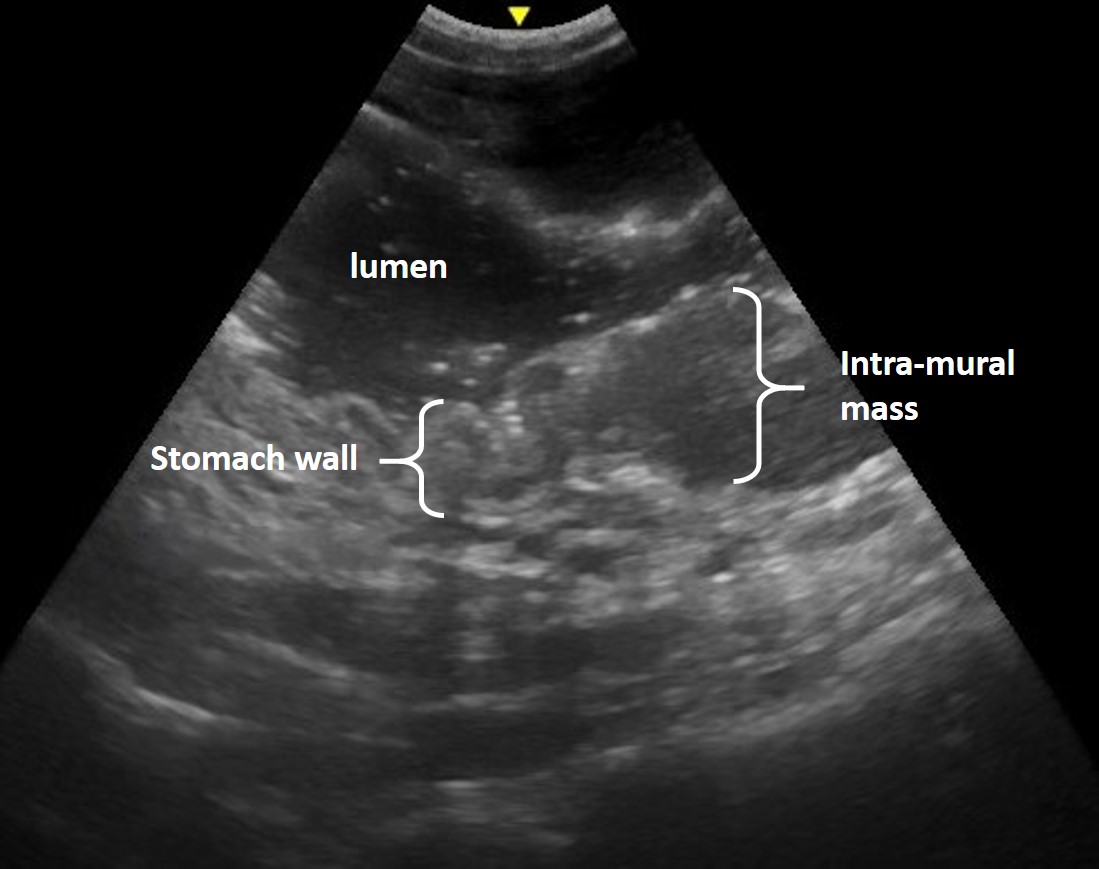

- Total wall thickness or changes in relative wall layer thickness (Figure 8, 9)

- Alteration in the relative echogenicity of the layers, particularly subtle changes to the mucosa

- Alteration in the pattern or distinction of wall layering (Figure 10)

Figure 9. Feline gastric lymphoma – The fluid-filled lumen of the stomach highlights the normal, layered appearance of the stomach wall in the left of the image. There is an intramural mass with associated loss of layering, thickened stomach wall and relative change in echogenicity to the right of the image.